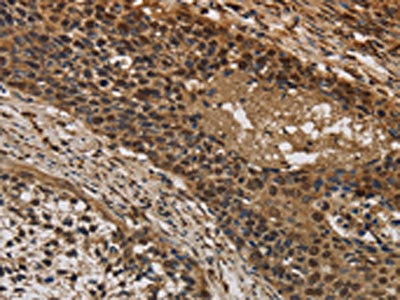

The image on the left is immunohistochemistry of paraffin-embedded Human cervical cancer tissue using CSB-PA299855(CYBA Antibody) at dilution 1/20, on the right is treated with synthetic peptide. (Original magnification: ×200)